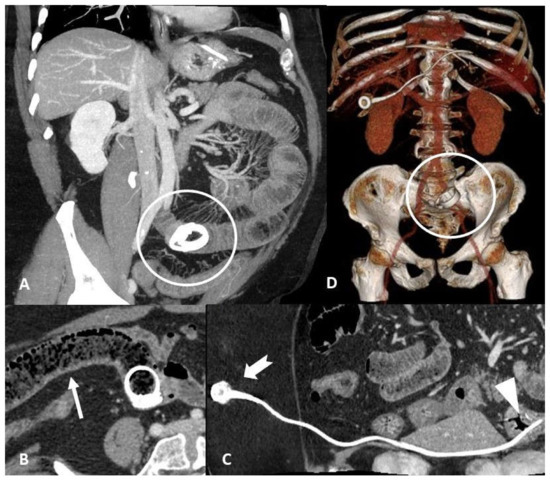

3. Device Integrity and Migration

4.3. Obstruction